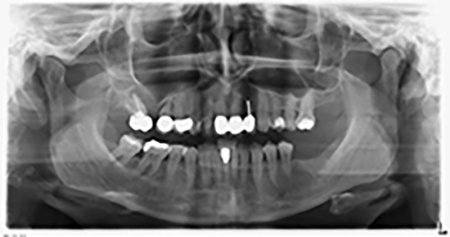

Die 59-jährige Patientin wurde mit einer fortgeschrittenen Parodontitis vorstellig, beschrieb ein ungutes Gefühl und einen schlechten Geschmack ausgehend vom ersten Quadranten distal. Die klinische Untersuchung zeigte allgemein erhöhte Taschentiefen und einen stark fortgeschrittenen Knochenabbau in regio 16 und 14. Die radiologische Untersuchung untermauerte den Befund (Abb. 1). Die Zähne 16 und 14 waren nicht zu erhalten.